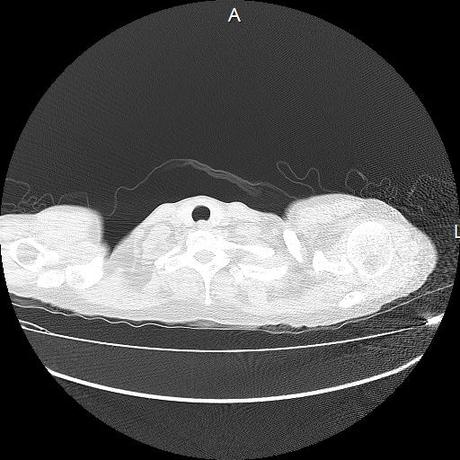

Se realiza volumen de tórax en fase simple, desde los opérculos torácicos hasta los hemidiafragmas, observándose:

Tejidos blandos sin evidencia de alteraciones.

Estructuras óseas sin evidencia de lesiones líticas, blásticas ni trazos de fractura. A nivel de cuerpo vertebral de T10 se observa nódulo de Schmorl que distorsiona el borde superior del cuerpo vertebral.

La tráquea es central, con adecuada columna de aire, sin evidencia de compresiones o desplazamientos.

El mediastino es central, sin evidencia de crecimientos ganglionares.

El corazón y los grandes vasos de morfología y situación normal.